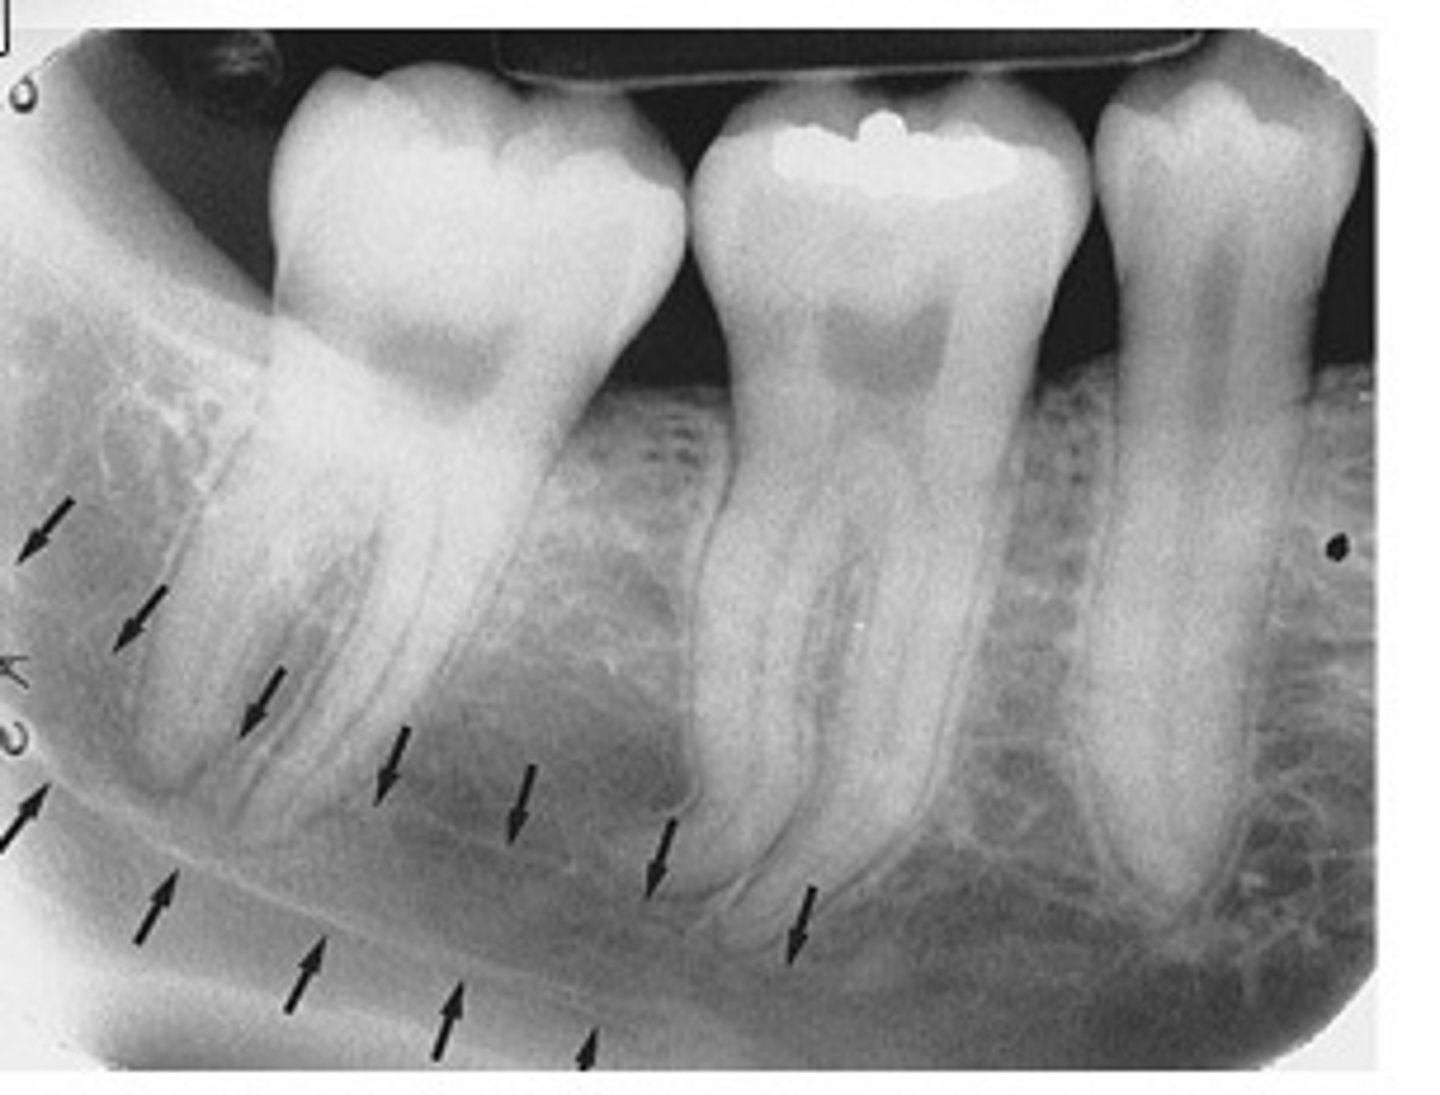

Nutrient canals

What is the radiolucent structure seen here?